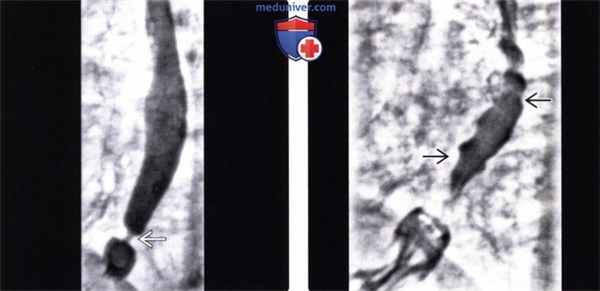

(Слева) На рентгенограмме, полученной во время рентгеноскопии пищевода у мужчины средних лет с возрастным нарушением моторики пищевода (пресбиэзофагус), визуализируется небольшая грыжа пищеводного отверстия диафрагмы, а также кольцо Шацкого, «отмечающее» область перехода пищевода в желудок.

(Справа) На рентгенограмме пищевода, выполненной при рентгеноскопии у этого же пациента, определяются периодические, очевидно, непропульсивные, третичные сокращения пищевода. Кольцо Шацкого и расстройство перистальтики привели к нарушению прохождения бариевой капсулы (на рентгенограмме не показана).

2. Рентгеноскопия при дискинезии пищевода:

• Видеорентгеноскопия с бариевой взвесью:

о Ахалазия

- Выраженная дилатация пищевода

- Отсутствие первичной перистальтики

- Деформация в виде «птичьего клюва»: V-образное, равномерное, коническое сужение просвета в области пищеводно-желудочного перехода

о Диффузный спазм пищевода:

- Первичная перистальтика определяется в шейном сегменте пищевода

- Периодическое «выпадение» первичной перистальтики в грудном сегменте пищевода с наличием фокальных облитерирующих сокращений

- Сокращения носят повторяющийся характер, при этом просвет пищевода принимает вид «штопора» или «четок»:

Сокращения пищевода часто сопровождаются болевыми ощущениями в грудной клетке

о Пресбиэзофагус или НРМП: множественные аперистальтические (третичные) сокращения и уменьшение выраженности первичной перистальтики

(Слева) На рентгенограмме пищевода в вертикальном положении, выполненной женщине 28 лет с первичной ахалазией, определяется значительное расширение просвета пищевода с наличием ровного конического сужения в виде «птичьего клюва» в его дистальных отделах.

(Справа) На рентгенограмме пищевода, выполненной этой же пациентке во время рентгеноскопии, определяется отсутствие первичной перистальтики, повторяющиеся вялые третичные сокращения, обусловливающие волнистый контур пищевода, просвет которого заполнен бариевой взвесью.